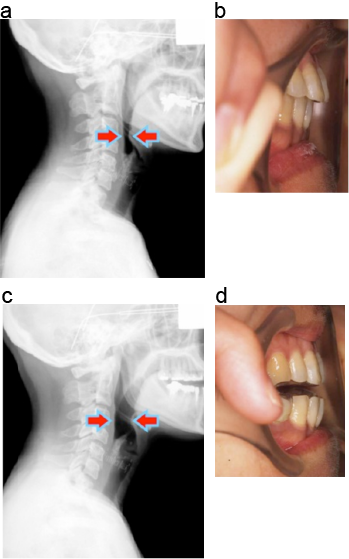

経口的にはMackenzie分類を用いる.

a:口蓋扁桃の肥大なし

b:Ⅰ度肥大:前後口蓋弓のなす面よりわずかに口蓋扁桃が突出している

c:Ⅱ度肥大:前後口蓋弓のなす面より口蓋扁桃が強く突出していて、Ⅰ度とⅢ度の中間の肥大

d:Ⅲ度肥大:口蓋扁桃が正中線を超えて突出している(または両側の口蓋扁桃が正中で接触している)